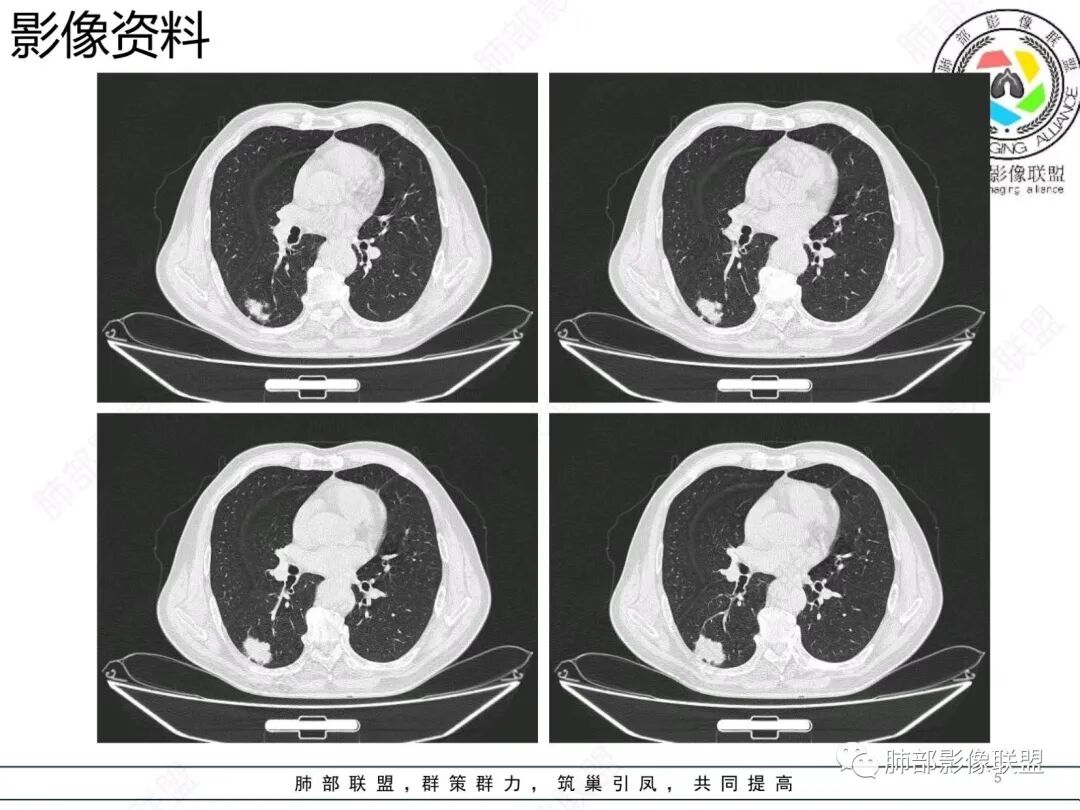

右肺下叶背段胸膜下肿块,边缘不规则,分叶,毛刺,有磨玻璃,边界清,近肺门侧见血管聚集,支气管进入后闭塞,右肺下叶肺静脉牵拉扭曲。诊断,支持腺癌

老年男性 右肺下叶胸膜下见一团状实性病灶+边缘磨玻璃,边缘形态不规则,,局部有平直,长轴平行于胸膜面,整体收缩力偏弱,邻近胸膜面轻度增厚,纵隔窗显示病灶内可见支气管充气,考虑炎性肉芽肿,隐球菌可能,鉴别黏液腺癌。

结节型粘液腺癌,具有血管弯,支气管截断,磨玻璃边界清楚等恶性征象,同时磨玻璃内部较糊,似清非清,不符合普通腺癌附壁生长特点,更像局限的粘液成分。收缩力不强,胸膜局部微积液,内部小空洞(考虑局部粘液排除形成),所以考虑结节型粘液腺癌。

区别1:结节期(影像说结节型)粘液腺癌,粘液成分还大多数局限于粘液腺癌细胞的胞浆中,没有飘出去,所以粘液密度不明显,周围的磨玻璃成分大多数还是分散于肺泡壁上的粘液腺癌细胞,所以边界相对较清楚(时间越晚,飘出去的粘液越多,边界就会越不清楚了),因为胞浆中的粘液成分显得较糊,有点似清非清。而普通腺癌附壁生长的腺癌细胞胞浆中没有粘液,所以非常清楚。

1.结节型肺粘液腺癌以中老年女性多见,单发,发病部位常位于两下肺胸膜下(肺外周带)。                2.多数病灶具备典型恶性肿瘤征象,但是不典型者仍不少见。可有分叶和棘状突起,但较少出现典型毛刺征。强化程度不如一般的腺癌病灶那么显著。          3.病灶常呈圆形或不规则形,实性结节略多于混合磨玻璃结节,少见于纯磨玻璃结节;或囊实性结节影或肿块,密度混杂,部分可出现钙化;病灶边界可清楚,也可模糊,须与炎性结节鉴别;周围可有类圆形磨玻璃密度卫星灶;表现为实性结节病灶,收缩力可能表现不明显,较少胸膜凹陷或血管集聚,须与良性结节鉴别。                                                     4.原发性肺粘液腺癌侵袭力相对较低,发展慢;病灶较少破坏支气管及血管,可表现为血管造影征及空气支气管征。较少胸膜侵犯,也较少肺门纵隔淋巴结转移。

1.病理基础:肺原发性粘液腺癌的肿瘤细胞产生大量粘液,聚集于细胞内,破入细胞间隙甚至肺泡、末梢细支气管,致使病灶密度增高呈混合磨玻璃或实性结节。                                                         2.粘液的直接扩散和漂移,致使病灶边界模糊和病灶呈多灶性生长。                                            3.粘液的重力效应致使病灶常位于胸膜下或叶间胸膜附近。                                                       4.病灶内气管、血管破坏不明显,可出现血管造影征及空气支气管征;也提示病灶侵袭力较低。           5.粘液的张力(占位效应)常可抵消病灶收缩力,致使病灶收缩力表现常较弱。